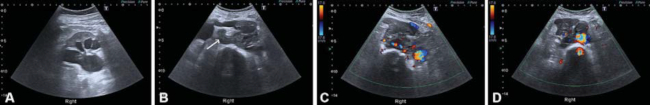

Al realizar el estudio, se observa un riñón derecho con dilatación pielocalicial y adelgazamiento cortical. El uréter proximal se encuentra dilatado hasta una masa retroperitoneal de gran tamaño y vascularizada, anterior a los cuerpos vertebrales y a la derecha de la aorta (►Fig. 1).